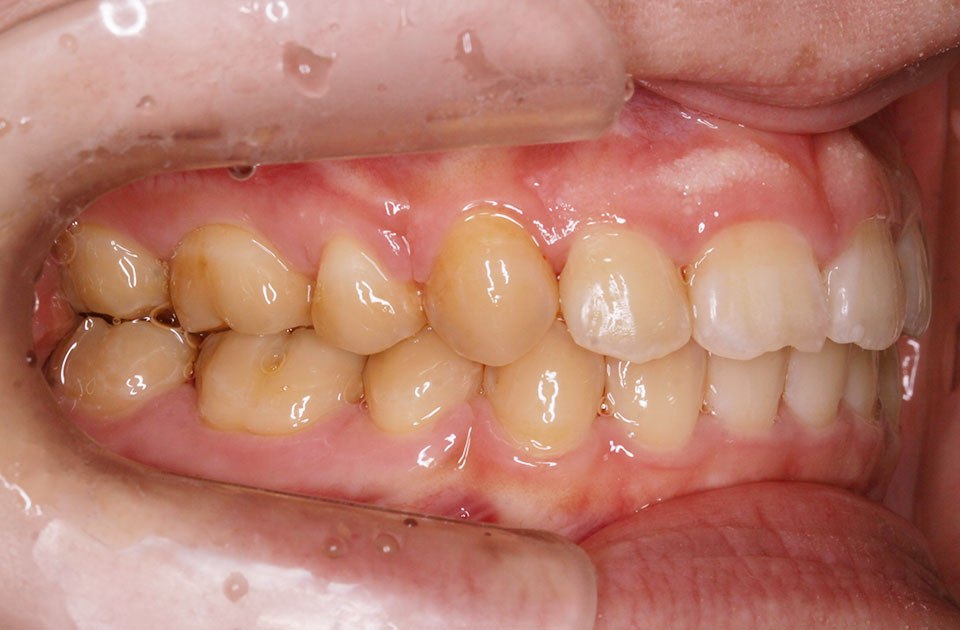

矯正前 左側

矯正後 左側